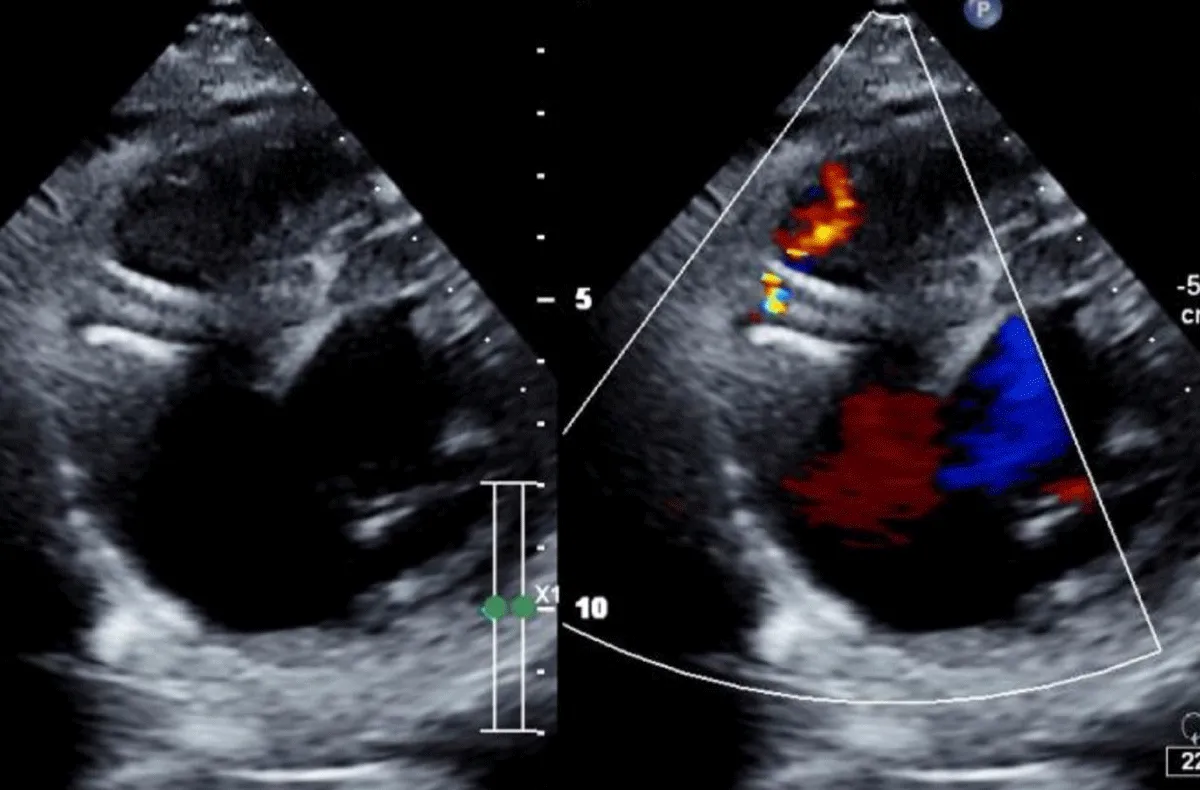

There was no use of transesophageal echocardiography due to the unavailability of a suitable probe. Left Ventricular angiogram was done to determine the exact location of the VSR (Figure 2). Cannulation of the right femoral artery and right internal jugular vein or right femoral vein was performed using the Seldinger technique. A guidewire (03500 Terumo guidewire) was introduced from the femoral artery, through the aorta into the left ventricle, and advanced through the VSR into the right ventricle and pulmonary artery. A second snaring wire was introduced through the vein (Either jugular or femoral) to connect to the guidewire in the pulmonary artery. By retracting the snared wires, the guidewire now forms an arteriovenous (AV) loop. The delivery sheath was advanced from the venous side loop over the guidewire through the VSR into the left ventricle. Correct positioning of the delivery sheath is confirmed in fluoroscopy/TTE. The guidewire is then retracted leaving the delivery sheath in position. After the echocardiographic confirmation occluder device was deployed across VSR using the delivery sheath (Figure 3). Correct positioning of the device and closure was confirmed by transthoracic echocardiography and/or fluoroscopy. If placement is satisfactory, the occluder is released. Post-procedure Left ventricular angiography and transthoracic echocardiography (Figure 4) were done to confirm the position and to rule out the presence of any residual shunt. We did not perform transoesophageal echocardiography for delineation of post-MI VSR, in any of the patients of our series due to the lack of availability of probes. In two cases we did not use any contrast agent (angiography) to delineate VSR because both patients had very high levels of urea and creatinine. Out of 11, in 10 cases, we made use of the femoral-jugular mode of access and created an AV loop. In one case we made a femoral arterio-venous loop. The veno-venous loop though described in literature was not used in this study.

Figure 4: Transthoracic echocardiography done to confirm the position and to rule out the presence of any residual shunt.